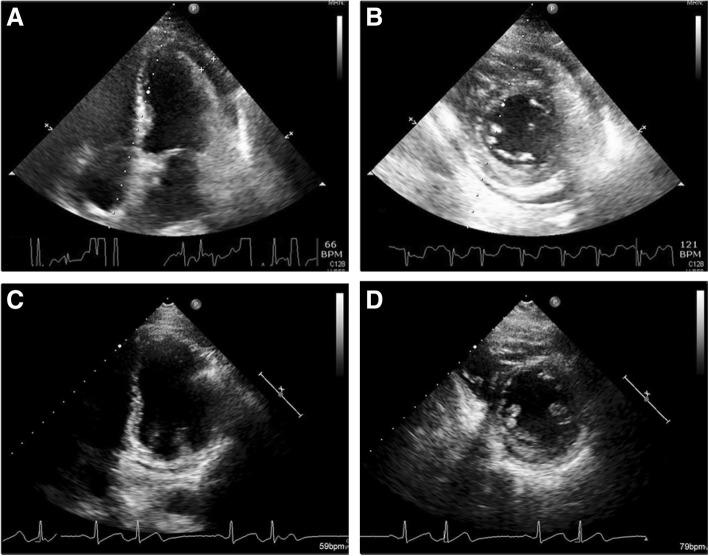

A 56-year-old man with underlying oral cancer received radiofrequency ablation for a metastatic liver tumor at segment II. Pleuritic chest pain developed on the day after radiofrequency catheter ablation. Diffuse ST elevation and echocardiography showed the new onset of small to moderate pericardial effusion without tamponade sign. Inflammatory markers were also elevated. Acute pericarditis due to heat penetration and stimulation was favored. His symptoms and signs resolved after treatment with anti-inflammatory medication.

一名患有口腔癌的56岁男性因肝Ⅱ段转移瘤接受了射频消融治疗。射频导管消融术后第二天出现胸膜炎性胸痛。弥漫性ST段抬高及超声心动图显示新出现少量至中等量心包积液,无心脏压塞征象。炎症标志物也升高。考虑为热穿透和刺激导致的急性心包炎。经抗炎药物治疗后,其症状和体征消失。